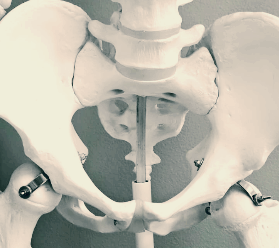

고관절은 대퇴골(허벅지뼈)과 골반이 연결되는 관절로, 신체 하중을 지탱하고 대부분의 움직임을 관여하는 중요한 부위입니다. 공 모양의 대퇴골두와 그를 감싸는 비구라는 구조가 만나 회전과 굴곡이 자유롭습니다. 고관절통증은 이 부위의 이상으로 인해 발생하며, 초기엔 증상이 뚜렷하지 않지만 점점 일상생활에 불편을 줍니다.

- 도수치료 및 체형교정: 잘못된 자세와 골반의 정렬 문제 해결